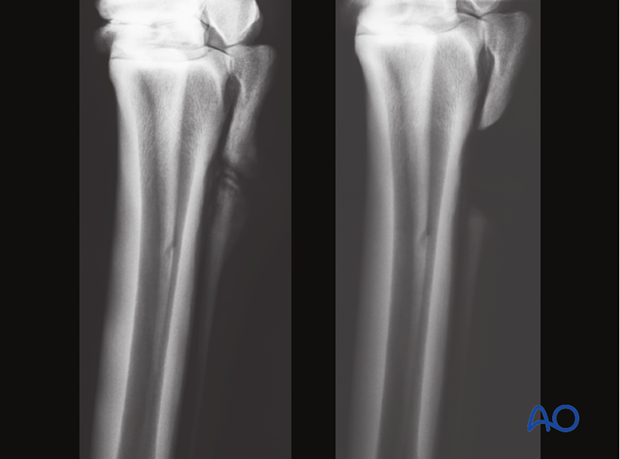

Clinical example before (left) and after (right) the segmental ostectomy.